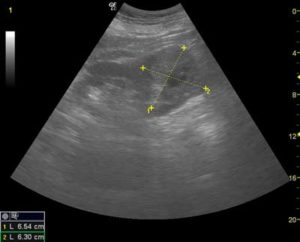

- Лучевая диагностика. Многие почечные образования хорошо визуализируются на КТ или при проведении УЗИ по поводу иного заболевания. При этом по визуализации можно разделить почечные новообразования на кистозные и солидные.

- Присутствие контрастирования. Главной отличительной чертой всех злокачественных солидных образований является наличие контрастирования. Как правило, для диагностики и характеристики различных образований почек применяют УЗИ, магниторезонансную и компьютерную томографию. Большинство из них можно точно диагностировать с использованием различных методик визуализации. УЗИ с контрастирующей жидкостью может быть показательным в особо сложных случаях, например, при ХПН с противопоказанием к использованию других контрастов.

- Визуализация на КТ и МРТ используется для уточнения характера образования. При этом важно получить изображение опухоли до и после введения контраста. Это позволит оценить контрастирование по шкале Хаунсфилда. Неоспоримым доказательством контрастирования является изменение контрастности опухоли не менее чем на 20 единиц.